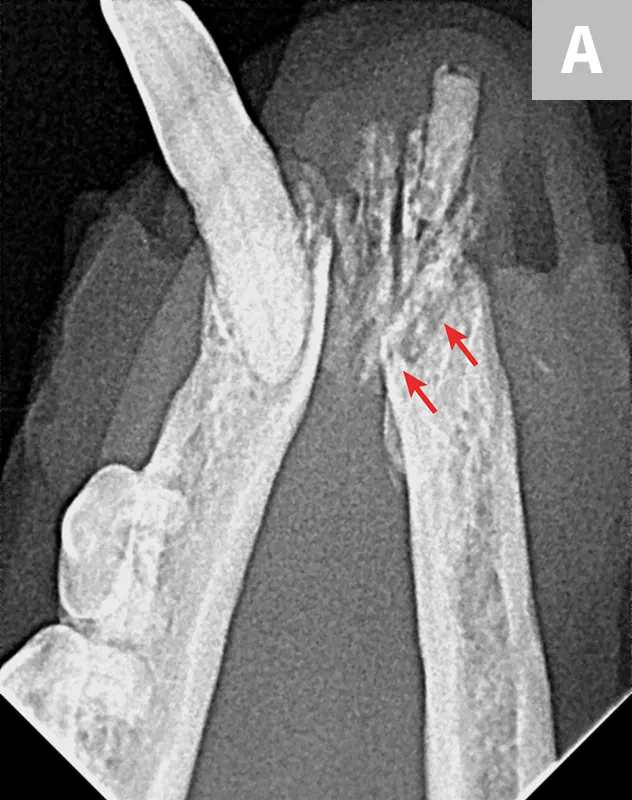

FIGURE 6

Iatrogenic fracture of the left rostral mandible after extraction of the left mandibular canine tooth (A; arrows). Same patient with iatrogenic jaw fracture after extraction (B); significant bone loss from periodontal disease was present, which contributed to this complication. Dilacerated root of the left mandibular first molar in a small-breed dog (C). The first molar in these breeds is often very large as compared with the width of the mandible. The hook on the mesial root can make extraction more challenging.

Small-breed dogs have a high first molar:mandibular height ratio, which increases the risk for fracture in cases of periodontal disease.14 In such cases, the roots can also be dilacerated (ie, there is an abnormal bend, hook, or overall shape to the root[s]); the tooth may have significant bone loss and appear to be an easy extraction, but the hook on the end of the root tip often makes removal much more difficult (Figure 6C).